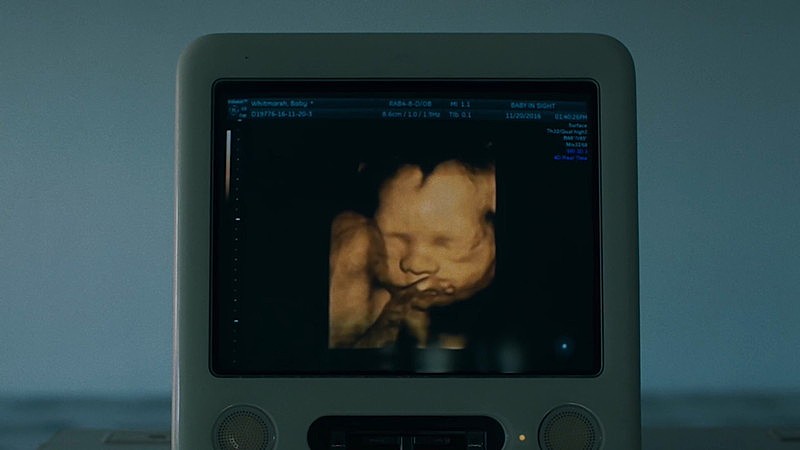

この楽曲は、聴く人により異なるそれぞれの視点を繋ぐことで違った景色が見えるのではとの構想から、秋田ひろむから見た景色を歌った楽曲。MVは様々なアーティストを手掛ける新進気鋭の作家・小島央大が担当。タイトル通り“世界の解像度”をキーワードに、人が世界を見る視点が大きく変わるような起点として“死”と“生”に直面する場面を軸に制作された。